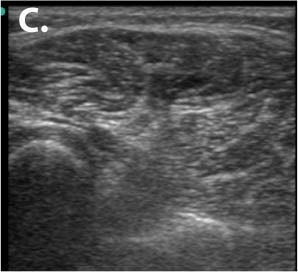

Figure 15 CRPS in a 26-yr-old after metacarpal fracture 18 months prior

Row 1- The ultrasound appearance of a normal muscle from the healthy limb. Note that the outlines of the muscles are clearly defined by shiny white borders and all the different muscles are identifiable and can be named. The muscles themselves have a dark background within a framework of supporting fibrous tissue which appears like shiny white streaks, and this is the typical sonographic signature of muscle. The second image shows her hand trying to make a fist, that she is unable to flex the fingers onto the palm or touch the tips of fingers to each other or thumb. Ultrasound of the CRPS limb in the 3rd image shows that there is no definition of muscle boundaries nor is there the normal contrast of black muscle in with white streaks of fibrous framework in between as compared to the ultrasound of the muscles of normal limb. In short there is a complete disruption of muscle structure.

2nd row- The first image shows that the patient has regained the ability to make a fist after 1month of USGDN of the forearm muscles. The patient opening the cap of a bottle 18 days after treatment which was impossible for her before USGDN at Ashirvad. Image C shows the return of normal structure to the muscles on ultrasound although there is still some predominance of fibrosis in the form of hyperechogenic fibrous streaks.

We found that these ultrasound changes of muscle structure disruption were consistently present in varying degrees in every patient that we examined thereafter. The USG changes of muscle abnormality appear as early as 15 days after the onset of CRPS and continue to be not just present but keep worsening till the muscle becomes completely fibrotic as indicated by the white-out appearance in all muscles affected by CRPS of medium or long duration. This was the picture that we saw in the first patient who had CRPS for 2 years. Subsequently we made it a part of our CRPS management protocol to routinely to document the muscle changes in every patient before USGDN, at 15 and 30 days and after the patient has recovered fully and correlate it with documentation of clinical findings.